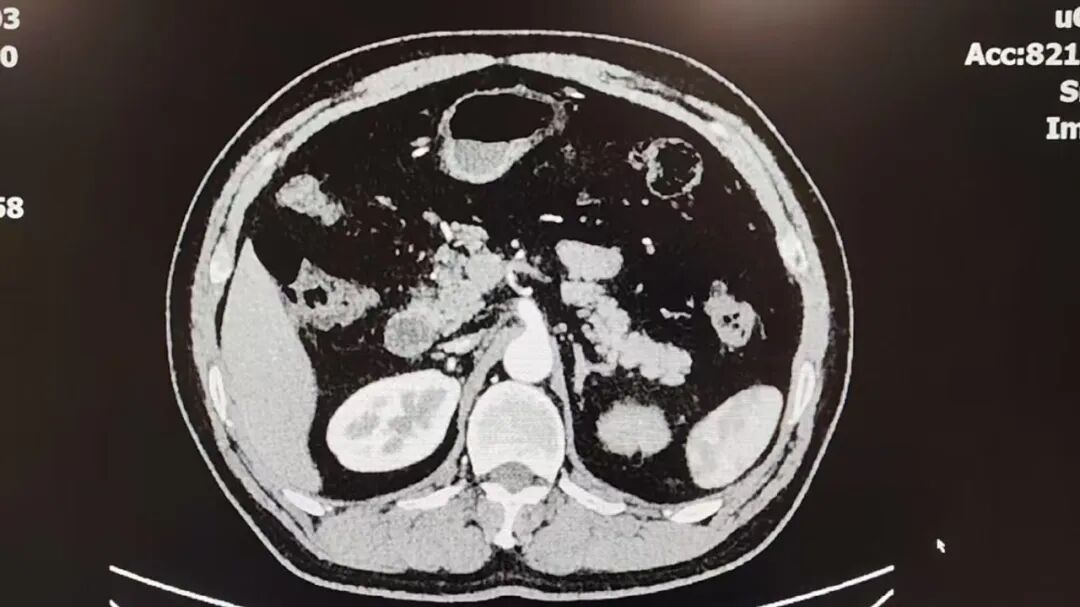

经过影像学检查,结果很快揭开了“血尿背后”的原因:左侧输尿管中段出现了占位性病变——疑似尿路上皮肿瘤。

考虑到陈先生同时有高血压等基础疾病,手术方案必须慎之又慎。科主任张鸿毅接手会诊,心血管内科、麻醉手术科、影像科等多学科团队迅速加入讨论。医生们一边反复确认检查结果,一边权衡风险与收益,为陈先生设计出合适的方案。

最终的结论是:在机器人辅助下行腹腔镜左侧肾输尿管切除术。

这是一场需要精细操作的手术,输尿管位置深、周围结构复杂,机器人技术能让切除更精准,也让创伤更小。